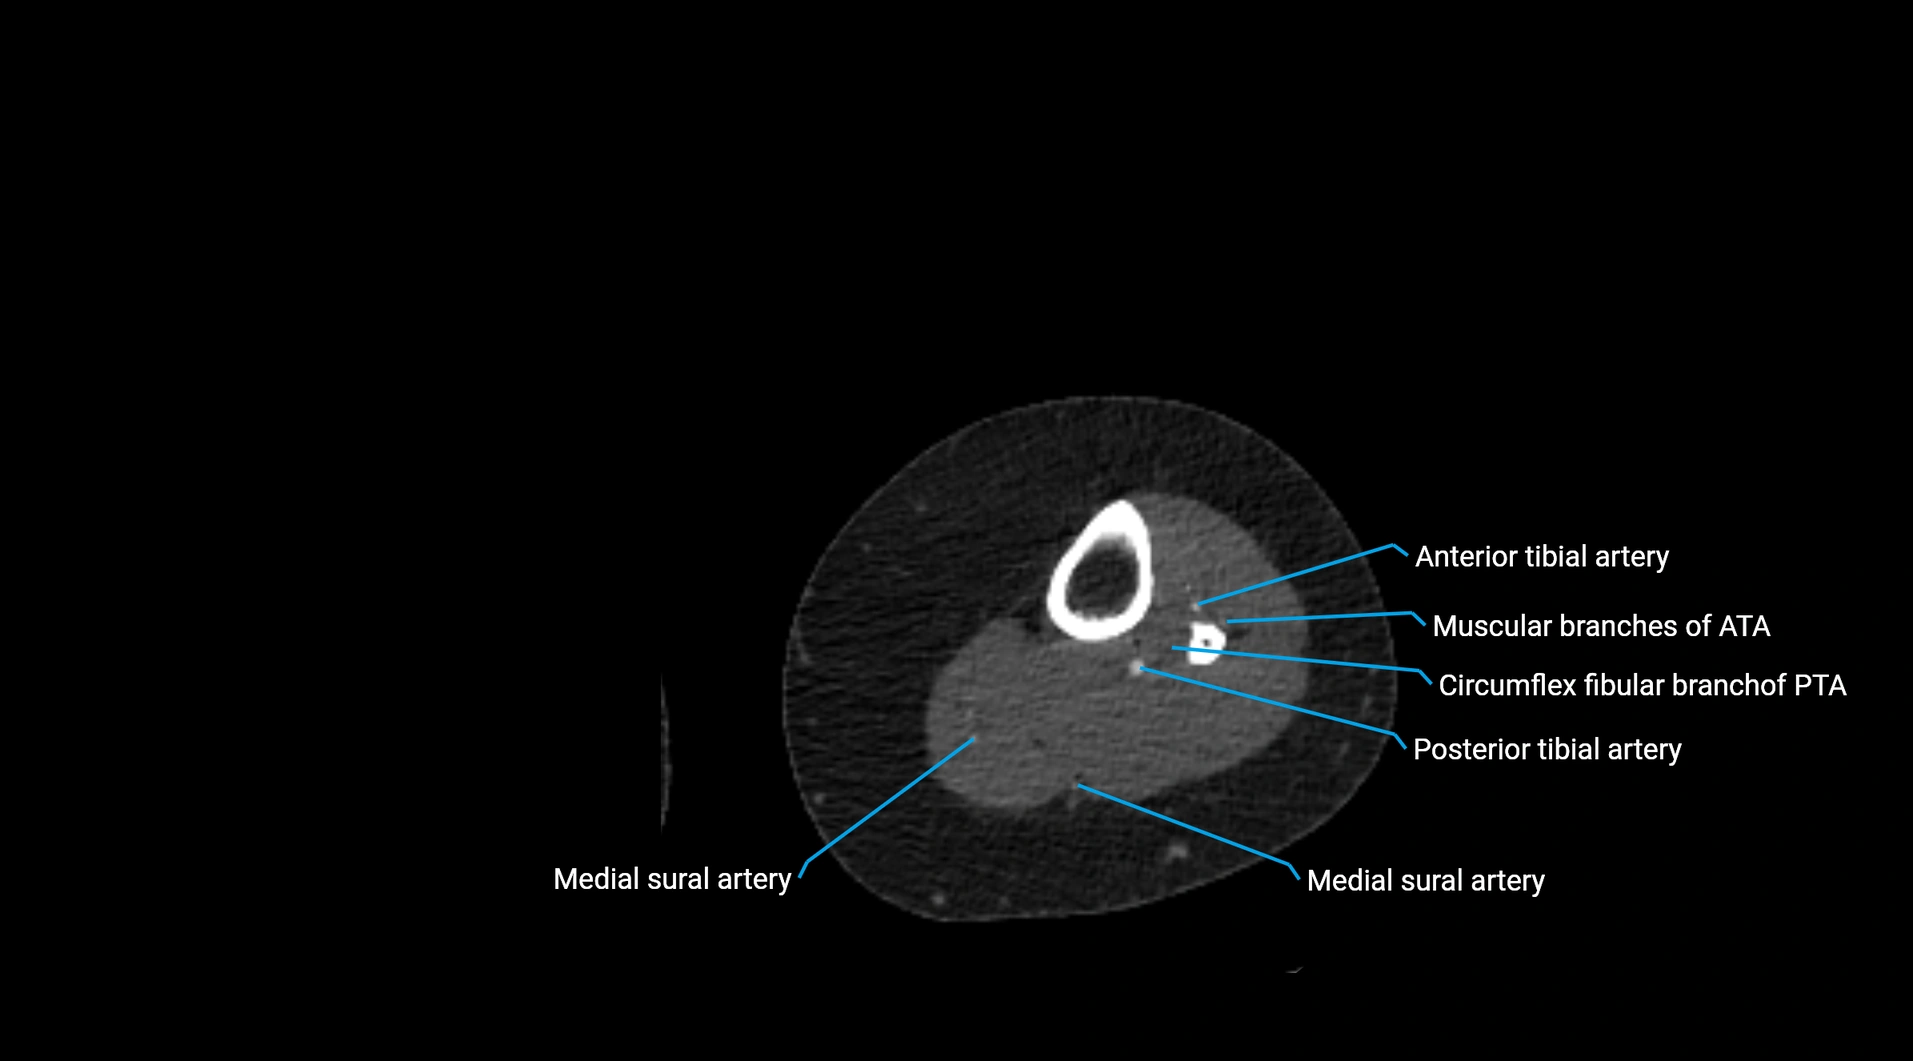

CT images

image